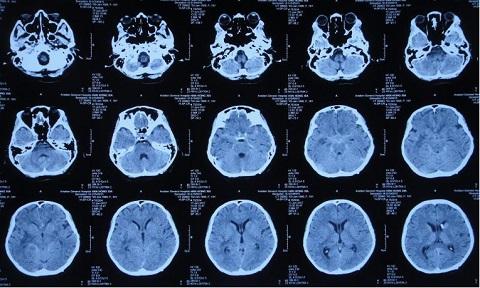

据患者家属介绍,患者入院2月前出现头痛、呕吐、发热症状,最高体温38.4度,至神木县医院急诊外科,检查途中突然出现四肢软瘫、呼喊不止,随即意识丧失、大小便失禁,紧急收入ICU,新腰椎穿刺检查:CSF常规:细胞总数1548×106/L,淋巴细胞百分比56.8%,蛋白2266mg/l,糖1.15mmol/l,考虑结核性脑膜炎,收入ICU。

8月16日,患者脑脊液仍然色黄浑浊,复查增强MRI现实四叠体池区、鞍区、环池内多发结核脓肿。

10月18日,患者脑脊液外观基本清亮,增强头MRI现实仍然课件鞍区多发结核脓肿、四叠体池、环池内病变明显改善。